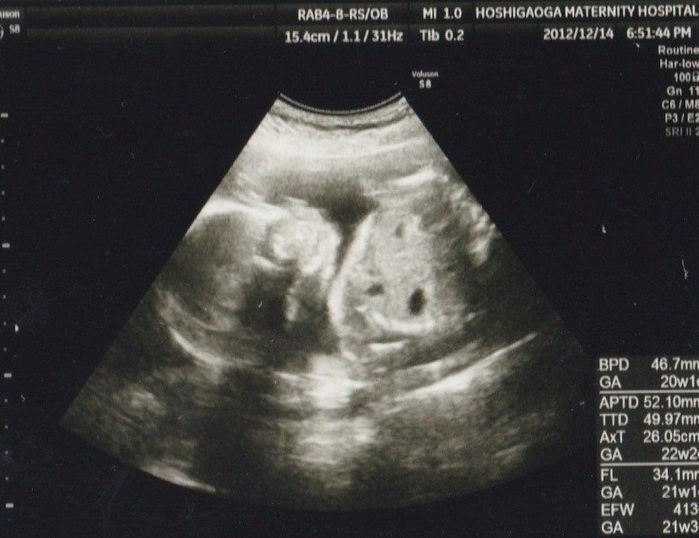

妊娠21週目のエコー写真

頭の左右幅は約46mm、推定体重は413gになりました。両方とも4週間前の約2倍になりました。左側に頭部、右側に胴体です。こちらからは横顔が写っているように見えます。少し前から長女との親子スイミングを再開。水中だと長女の体重でおなかに負担がかかることも気にせず、たくさん抱っこしてあげられるので、私たちにとって特別な時間でした。